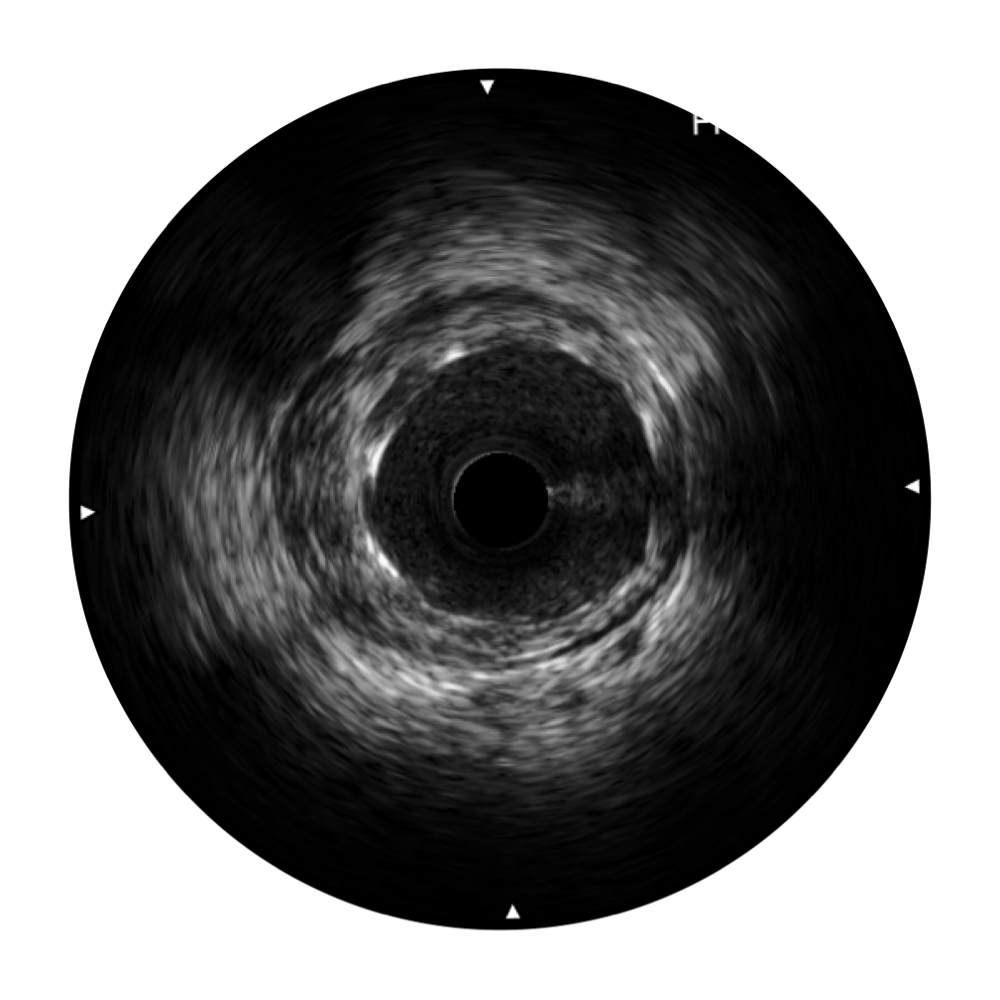

• 环球UG官网宽频IVUS图像

• 传统IVUS图像

对比传统IVUS导管成像,环球UG官网宽频IVUS图像的近场支架梁显影更细腻,远场中膜外血管仍清晰可辨,兼顾远中近,兼顾分辨力与穿透深度